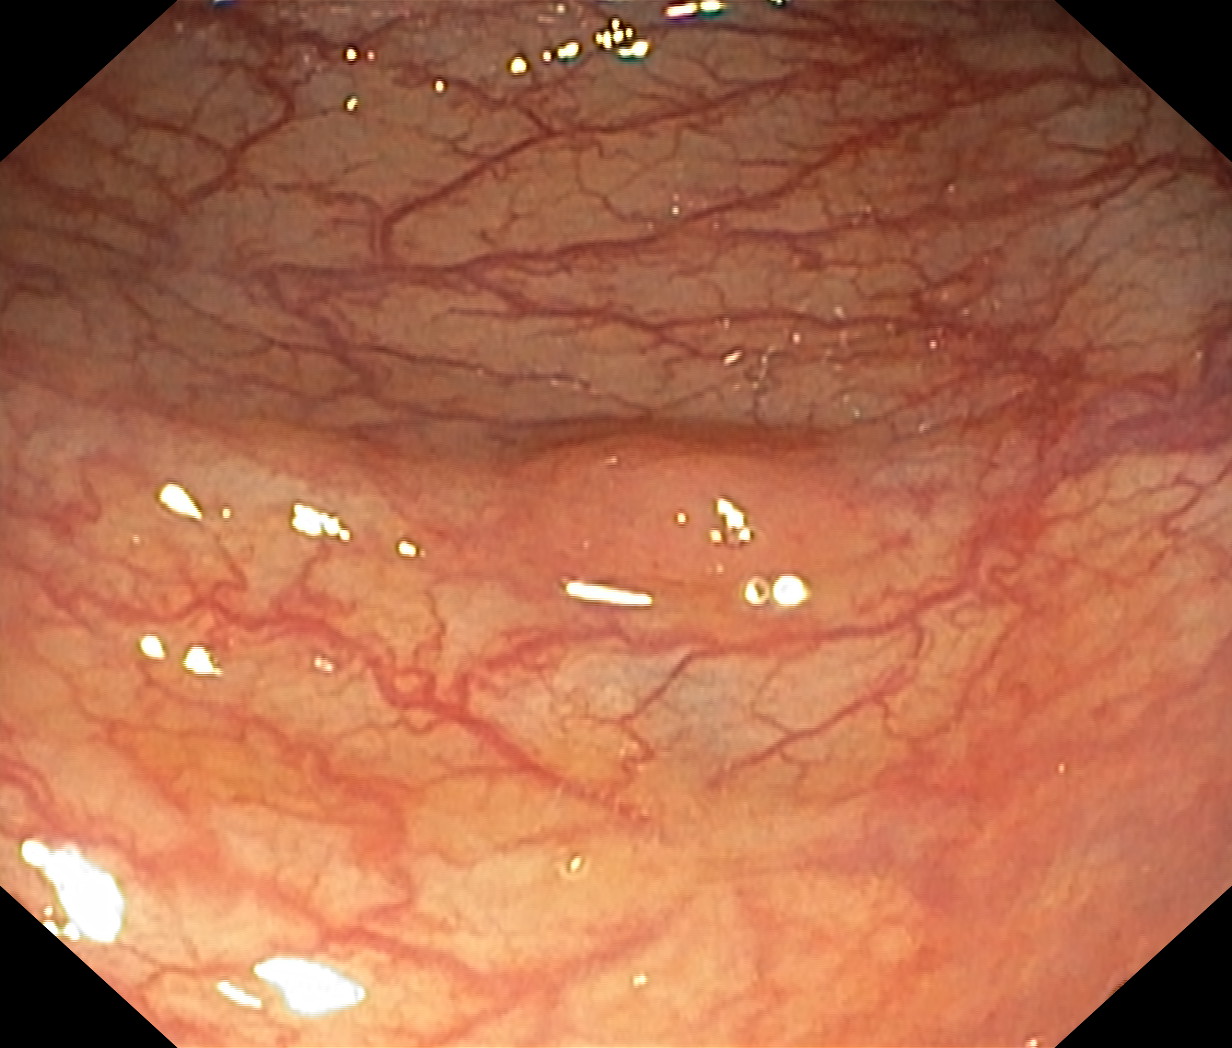

As part of the EndoCV2021 challenge (https://endocv2021.grand-challenge.org/), we were tasked with creating machine learning models that automatically segment polyps [11, 12, 13] in video frames collected from real-world endoscopies. This is a complex task as polyps come in various shapes and sizes, where some (e.g., flat lesions) are barely detectable by even the most experienced endoscopists. Figure 1 shows some of the more difficult examples taken from EndoCV’s development dataset [10] provided by the challenge organizers. The challenge presented two separate tasks, the detection generalization challenge and the segmentation generalization challenge. We participated in the segmentation generalization challenge, where we achieved the best results among 13 other competitors in both rounds. The code for the experiments presented in this paper is available on GitHub111https://github.com/vlbthambawita/divergent-nets.